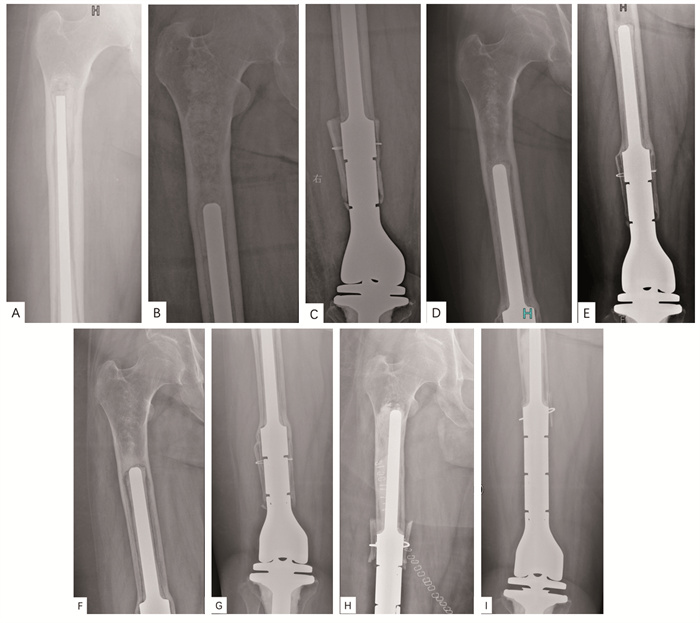

![]() 图 2 一例出现再次松动患者的影像学资料Figure 2 Imaging data of one patient with repeated aseptic looseningA: longitudinal position of the prosthesis stem before the revision; B-C: three months after revision, shorter and thicker stems were selected; D-E: 33 months after revision, the porous coated bone grew into part of the bridge and healed well; F-G: 118 months after revision, repeated aseptic loosening; H: immediate X-ray image after repeated revision, the porous coated bone bridge technique was used again; I: X-ray image 22 months after repeated revision, no sign of aseptic loosening.

图 2 一例出现再次松动患者的影像学资料Figure 2 Imaging data of one patient with repeated aseptic looseningA: longitudinal position of the prosthesis stem before the revision; B-C: three months after revision, shorter and thicker stems were selected; D-E: 33 months after revision, the porous coated bone grew into part of the bridge and healed well; F-G: 118 months after revision, repeated aseptic loosening; H: immediate X-ray image after repeated revision, the porous coated bone bridge technique was used again; I: X-ray image 22 months after repeated revision, no sign of aseptic loosening.2.3 翻修假体的肢体功能